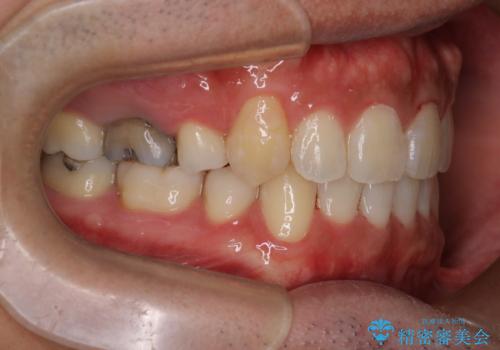

初診時の歯並びの状態としては、右上の犬歯がいわゆる八重歯の状態であり、強いガタガタが上下ともにある状態でした。

スペースの不足量が多く、抜歯を伴うワイヤー矯正にて治療を行いました。

若干の口元の突出感もあったため、抜歯によるスペースを利用し、がたつきの改善と前歯の後退をを行いました。